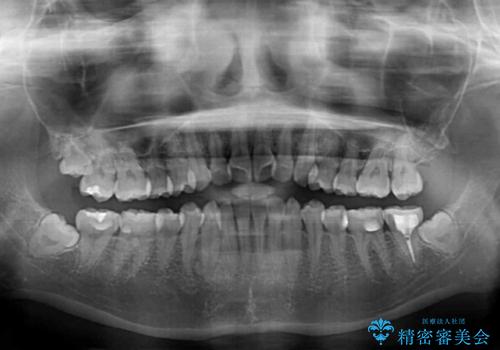

前歯のクロスバイト ワイヤー装置を併用したインビザライン矯正

- 前歯の捻転とクロスバイトが気になり、インビザラインによる矯正治療を希望して来院された患者様です。

上顎側切歯(上の真ん中から2番目の歯)が舌側転位している場合、インビザラインでは仕上げきれないことが多く、更には無理して動かそうとすると歯髄壊死を起こすリスクが高いと言われています。

インビザラインで歯列を移動する前に、上顎前歯をワイヤー矯正で整え、その後上下歯列をインビザラインにて矯正治療を行うこととしました。

舌側転位している側切歯特有の、切縁の位置が不揃いであったり、根元が内側に引っ込んだ状態であったりという、インビザライン独特の仕上がりになることなく、きれいに整った歯列とすることができました。